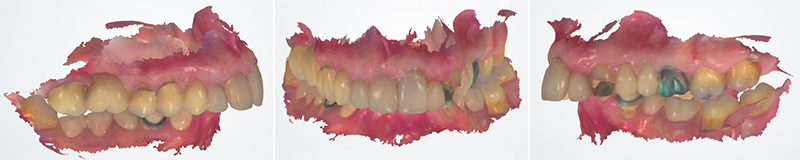

L’examen intrabuccal met en évidence une arcade maxillaire étroite caractérisée par la présence de prothèses conjointes dento-portées unitaires et plurales iatrogènes. L’arcade mandibulaire présente des édentements postérieurs compensés par une prothèse amovible partielle en résine.

Fig. 02 : photographie intra-orale et IOS initiaux, vue occlusale maxillaire et mandibulaire.

L’analyse fonctionnelle objective une classe II dentaire droite et gauche avec surplomb incisif augmenté et supraclusion associée à une morsure palatine.

Fig. 03 : IOS initial, rapports occlusaux latéraux et frontaux.